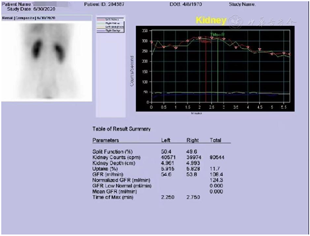

2020年6月30日肾核素显像ECT组套(肾动态+肾小球滤过率)。检查所见:患者床边弹丸式静脉注射药物后即行肾小球滤过率测定,经计算机处理,结果如下:左肾肾小球滤过率=54.6 ml/min,右肾肾小球滤过率=53.8 ml/min,双肾总肾小球滤过率=108.4 ml/min。双肾总肾小球滤过率本院正常参考值:105±25 ml/min(图3)。